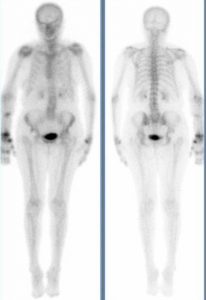

Temps vasculaire: hypervascularisation de la main droite. Temps parenchymateux: hypercaptation diffuse de la main droite.

Temps osseux: hyperfixation diffuse de la main et du poignet droits. Hyperfixation focale de l’extrémité distale du radius droit.

Hypervascularisation du poignet et de la main droite.

hyperfixation diffuse du poignet et de la main confirmant l’algodystrophie.

Hyperfixation focale du site fracturaire qui témoigne de la consolidation incomplète de la fracture

Algodystrophie du membre supérieur droit